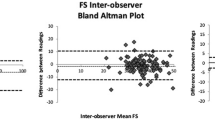

Intra- and inter-observer agreement and reliability of LWFS

The bias and LOA for intra-observer measurements of LWFS were 0.219 [-0.182, 0.621] and ± 3.539, respectively. The ICC was 0.91 [0.87, 0.94]. These indicate non-bias agreement and good intra-rater reliability. On the other hand, very small but insignificant bias was observed between two independent observers (bias = 0.589 [0.000, 1.176] and LOA = 3.196). Good inter-rater reliability was observed (ICC = 0.93 [0.91, 0.94]).